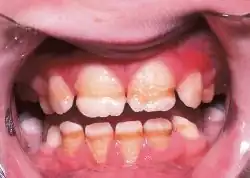

Enamel hypoplasia is a defect of the teeth in which the enamel is deficient in quantity,[1] caused by defective enamel matrix formation during enamel development, as a result of inherited and acquired systemic condition(s). It can be identified as missing tooth structure and may manifest as pits or grooves in the crown of the affected teeth, and in extreme cases, some portions of the crown of the tooth may have no enamel, exposing the dentin.[2] It may be generalized across the dentition or localized to a few teeth. Defects are categorized by shape or location. Common categories are pit-form, plane-form, linear-form, and localised enamel hypoplasia.[3][4][5] Hypoplastic lesions are found in areas of the teeth where the enamel was being actively formed during a systemic or local disturbance. Since the formation of enamel extends over a long period of time, defects may be confined to one well-defined area of the affected teeth. Knowledge of chronological development of deciduous and permanent teeth makes it possible to determine the approximate time at which the developmental disturbance occurred.[6] Enamel hypoplasia varies substantially among populations and can be used to infer health and behavioural impacts from the past. Defects have also been found in a variety of non-human animals.[7][8][9]